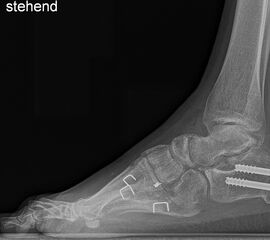

Knick-Senk-Platt-Fuß Korrektur mit dem Canalis Tarsi Spacer

In der Korrektur des schmerzhaften, aber flexiblen Knick-Senk-Fußes oder Plattfußes ist die Schraubenarthrorise mit einem Sinus tarsi oder besser bezeichnet als Canalis tarsi Spacer und alternativ mit einer Calcaneus-Stopp-Schraube seit vielen Jahren ein etabliertes Verfahren und führt zu einer kompletten Korrektur von flexiblen Knick- und Plattfuß-Fehlstellungen (Abb. 7). Die nötige Schnittlänge über dem Sinus tarsi beträgt für beide Verfahren 1 cm.

Abb. 7 a-e: Knick-Senk-Fuß prä- und postoperative Situation (a-b), ventrale und dorsale Ansicht (c-d). Laterale Ansicht des Hautschnittes über dem Sinus tarsi (e).

Zum Lesen der Bildbeschreibung und zur Vollansicht bitte die Bilder anklicken. Bilder: A. Helmers.